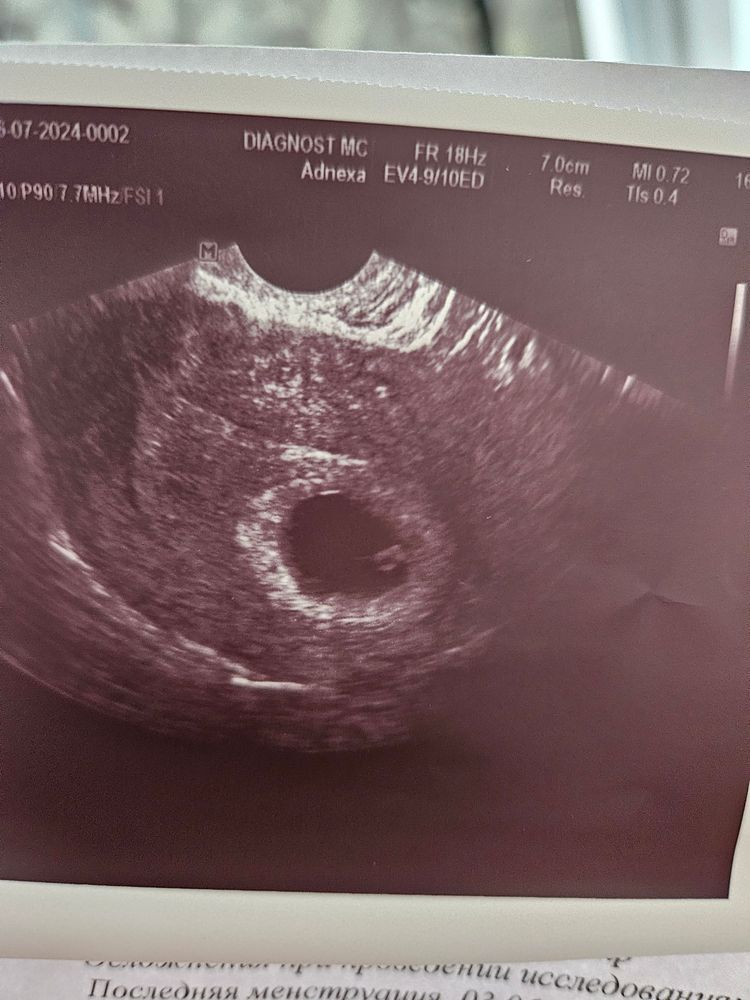

квитка, мне узистка сказала прямым текстом, что не видит жм, плодное походу пустое, потом через 2 минуты крутя туда сюда сказала , что все таки его видит. Я как понимаю вот этот пузырёк и есть жм , тогда и вопрос как она не заметила его ? Срок у меня 6,1 , а ставят 4-5 недель , вот и насторожило. А так конечно все так ,😅

Lerchik , я закровила на 22 дпп, помчала на уши в ближайшую частную клинику,моя врач не отвечала, вообщем я тогда вообще ничего не понимала в этих мешочках) намеряла мне она огромное плодное яйцо расплющила его просто датчиком, увидела эмбрион 1мм с пульсацией,я сижу параллельно форум читаю,спрашиваю,а желточный мешочек есть? Она говорит -нет😅 я с панической атакой на форум сюда пост писать) в и тоге попа к своей ре на 27 дпп, все нашли,что было не обходимо, на снимке вашем я вижу и ЖМ и эмбрион

Lerchik , вот он) Изображение

квитка, да и я написала 3 мм жм , что нашла и измерила ....